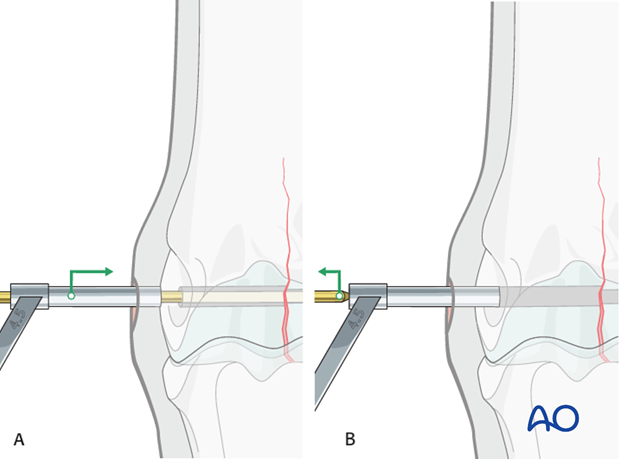

The 4.5 mm drill guide is subsequently placed over the 2.5 mm pin (A). The pin is removed (B) ...

... and the 4.5 mm tap inserted through the guide (C).

The hole is tapped routinely, keeping the very dense bone in mind. It is critical to tap completely through the far cortex (red circle). The bone is so dense that even a single millimeter of untapped bone may prevent complete insertion and tightening of the screw.

A long tap is strongly preferred to avoid impinging the end of the drill on the edge of the drill guide (yellow circle). This could result in stripping the threads in the hole or breaking the tap.